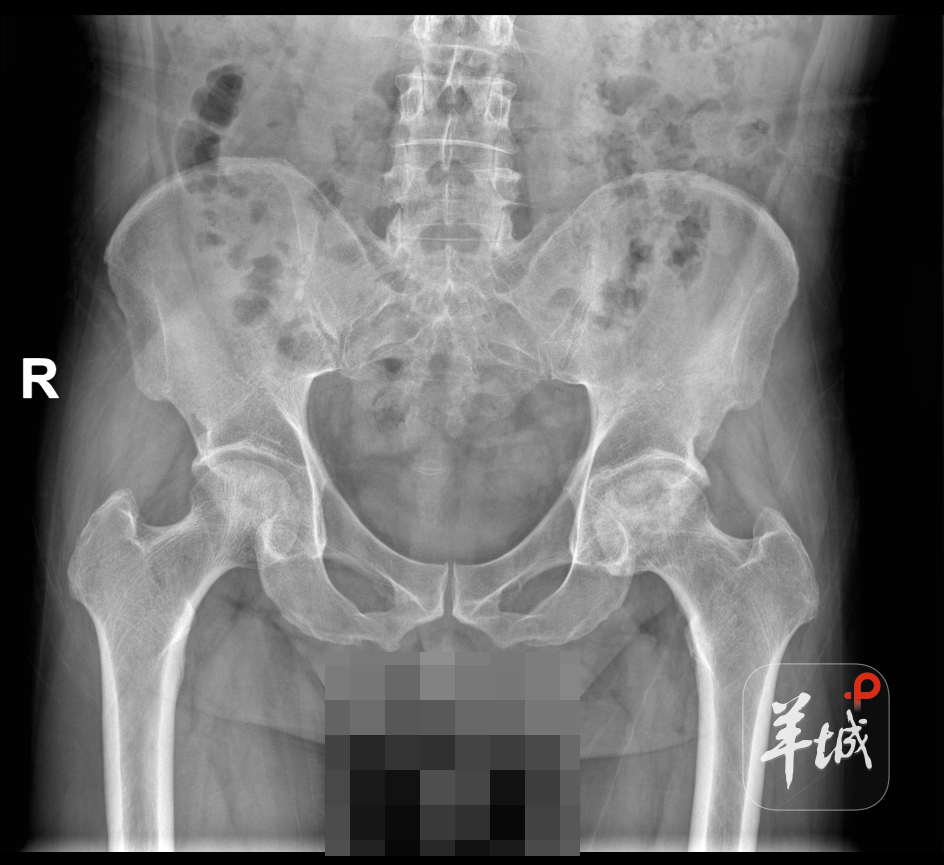

患者黄先生(化名)9年前接受心脏移植手术,术后需长期服用激素及免疫抑制剂维持心脏功能。然而,长期用药导致了药物性股骨头坏死并发症,左侧股骨头逐渐缺血坏死。剧烈的关节疼痛和活动受限使他出现保护性跛行步态,迫切渴望恢复正常行走能力。但心脏移植后需要精心维护的脆弱心功能、免疫抑制状态可能带来的高感染风险,以及合并的高血压、糖尿病、痛风、肾功能损伤等问题,为髋关节置换手术设下了重重障碍。

手术当天,针对患者心脏移植术后特殊体质,团队实施了术前术中个体化止血方案,有效减少出血,保护心脏功能。麻醉团队操作精准,术中生命体征平稳。主任医师张洋主刀,精准切除病变股骨头,高效完成髋臼打磨与假体植入,多维度验证关节稳定性。得益于完善的术前规划和默契的团队协作,手术过程顺利,未出现异常出血及循环波动。